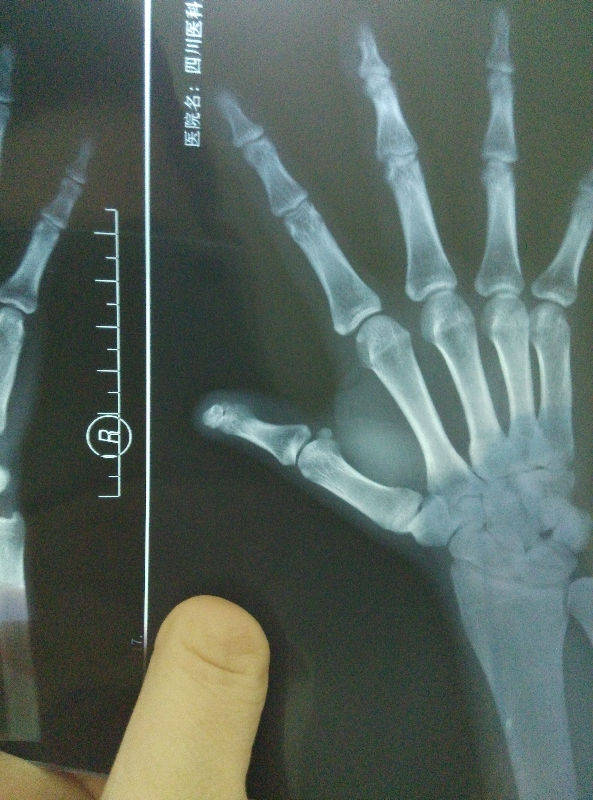

池老师,以下这个做再造效果怎么样呢

IMG_20150929_211059.jpg

IMG_20150929_211002.jpg